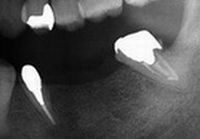

その際にはお痛みの原因となっていた歯の根の治療の後、新しいブリッジを装着しました。本日はそのブリッジが外れていらしたのですが、それもそのはずです。このブリッジは仮着(仮止め)用のセメントで装着していました。

仮着3ヵ月後に咬み合わせ・セメントの状況などを確認してから長期使用耐性のあるセメントで再装着する予定でした、もちろん患者様にも了解済みでした。

何故なら、咬み合わせは経年的に変化していきますので、良好な治療経過を維持していくためには、その変化に対応していくことが欠かせません。

しかしながら患者さま曰く、当初のお痛みも消え去りブリッジもとても快適だったとのこと、仮止めのこともメンテナンスのこともすっかりお忘れのご様子でした。私たちの心配とは裏腹に、歯根の大きな病巣は良好な術後経過であることを知ることとなりました。